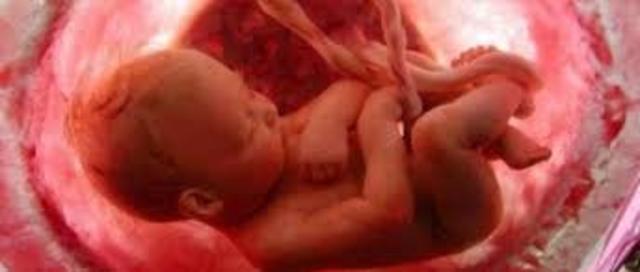

Video:Día 1-28El embarazo humano comienza con la fusión de un óvulo y un espermatozoide, a este proceso se le llama fecundación, cuando el óvulo es fecundado, un nombre mas apropiado es el de embrión. Éste ha de entrar al útero, donde se sumerge en la capa de revestimento interno del útero para ser nutrido por la madre.

Embrión bilaminar con saco vitelino primario.

En el doceavo día, el trofoblasto está formado principalmente por grandes masas de sincitiotrofoblasto activamente invasor, aunque también puede verse bajo el embrión una capa interna única de citotrofoblasto.